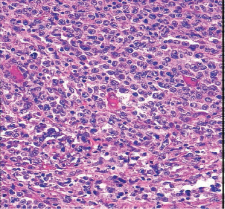

A morfologia, padrão-ouro de qualquer análise inicial: citológica, através da análise microscópica das células, e histológica, através da análise dos tecidos, é agora complementada por uma abordagem multidisciplinar: biológica e genética, de acordo com os critérios da OMS. Estas técnicas dispendiosas ainda não estão totalmente acessíveis aos países de rendimento baixo e médio, agravando as desigualdades no acesso aos cuidados de saúde nesses países.

Atualmente, esta última é realizada através da transmissão pela Internet de imagens microscópicas digitalizadas (imagens jpeg). Estas imagens são selecionadas por citologistas ou anatomopatologistas locais que utilizam um microscópio com uma câmara digital ligada a um computador e a uma plataforma de intercâmbio científico, a plataforma «i-Path», ligada à rede INCTR (International Network for Cancer Treatment and Research). Esta plataforma inclui vários grupos de intercâmbio científico constituídos por médicos identificados (hematologistas, anatomopatologistas, clínicos) em ligação com um grupo de especialistas internacionais nas diferentes áreas do cancro. Estes últimos comentam as imagens, ajudando os intervenientes locais a estabelecer um diagnóstico.

- Imunohistoquímica em corte.